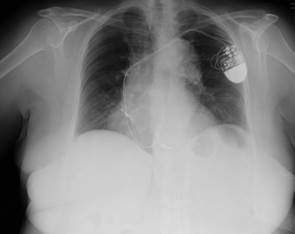

Mujer de 75 años diagnosticada de insuficiencia mitral moderada-severa por prolapso valvular, con indicación de cirugía por sintomatología de insuficiencia cardiaca progresiva hasta encontrarse en estadio clínico avanzado. Como antecedentes personales la paciente presentó intervención de implante de dispositivo de marcapasos (Sorin Group®) bicameral por disfunción sinusal hace ocho años, previo a la cirugía actual, manteniendo desde entonces controles periódicos del dispositivo. No manifestó otros antecedentes relevantes ni operaciones cardiacas previas. En el estudio prequirúrgico básico se realizaron pruebas preoperatorias de rutina incluido un electrocardiograma que mostró ritmo de marcapasos sin alteraciones y una radiografía de tórax (Ver Figura 1 y 2). El marcapasos bicameral funcionaba de manera correcta en modo DDD en la telemetría preoperatoria.

Figura 1 Radiografías de tórax antero-posterior prequirúrgica. Se observa correcta colocación de electrodos de marcapasos.

Figura 2 Radiografía de tórax lateral prequirúrgica. Se observa adhesión de los electrodos de marcapasos a la tabla interna del esternón.

Afortunadamente, no existen muchos casos similares descritos que impliquen lesiones de estructuras en la esternotomía media y el que aquí se presenta es el único que conlleva lesión de un electrodo de estimulación cardiaca con la sierra de esternotomía. Se pudo observar una gran fibrosis con adhesión del tronco venoso braquiocefálico a la tabla interna del esternón, visible en la radiografía prequirúrgica por lo que, con una exhaustiva revisión de las pruebas complementarias pudo haber sido evitado.

La creación de adherencias de los electrodos de estimulación cardiaca en los lechos vasculares en los que se alojan, es una entidad que debe tenerse en cuenta en todos los pacientes portadores de dispositivos cardiacos. La revisión cuidadosa de la radiografía torácica prequirúrgica en casos de implante previo de dispositivos cardiacos podría orientar en la sospecha de fibrosis o adherencias esternales que puedan representar un inconveniente para la realización de esternotomía.